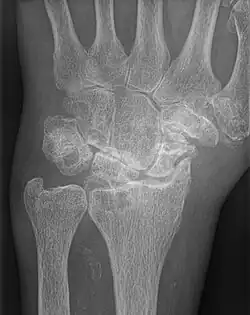

| AP wrist x-ray demonstrating Stage III scapholunate advanced collapse | |

Stage III SLAC wrist

Stage III SLAC wrist involves the entire radioscaphoid joint and the capitolunate joint.[3] The PA wrist x-ray will demonstrate sclerosis and joint space narrowing between the lunate and capitate. Over time, the capitate will migrate proximally into the space created by the scapholunate dissociation.[2] The radiographic findings in Stage III SLAC wrist are synonymous with the Terry-Thomas sign, indicating complete scapholunate dissociation.[2]